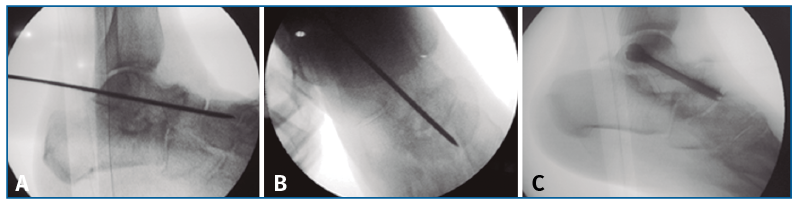

Finalmente, se realiza la osteosíntesis a compresión con un tornillo (ICOS® 6,5 mm; un caso con tornillo HCS® Synthes 6,5) primero de la TN (Figura 3) y después de la ST (Figura 4)(29)(30).

Figura 3. Reducción y fijación con aguja guía de la articulación astrágalo-escafoidea bajo control fluoroscópico en lateral (A) y anteroposterior (B) y osteosíntesis a compresión con un tornillo (C; ICOS® 6,5 mm).